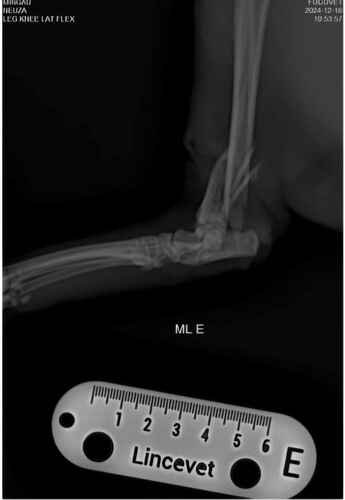

Ola, me chamo william estou criando essa vakinha para ajudar nos custos da cirurgia do mingau.Mingau é um gato que mora na rua e todos cuidam dele, mas nessa sexta feira dia 13/12 ele foi atropelado quebrou dois lugares na pata e passou por cirurgia hoje (16/12) e o custo da cirurgia ficou no valor de 1500 reais.infelizmente não temos esse dinheiro para estar pagando, já demos um abrigo para ele para se recuperar com segurança e bem alimentado